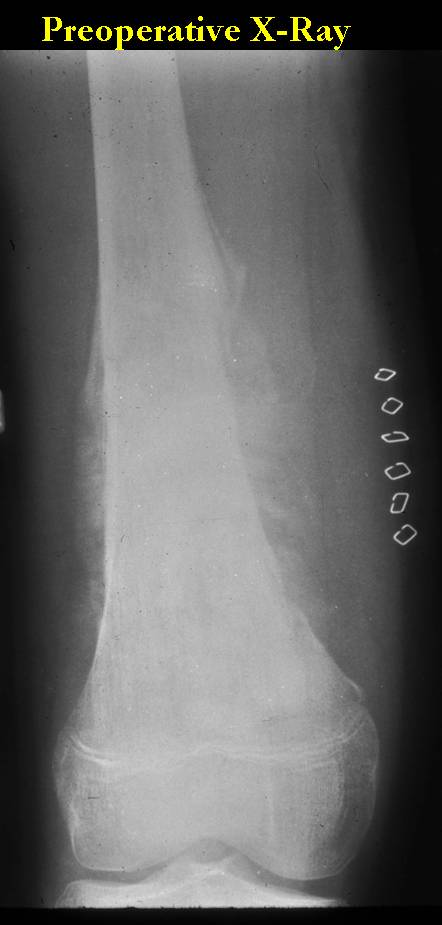

| Proximal Tibia Osteosarcoma: Limb-Sparing Surgery |

Intraoperative photos

Postoperative X-Rays